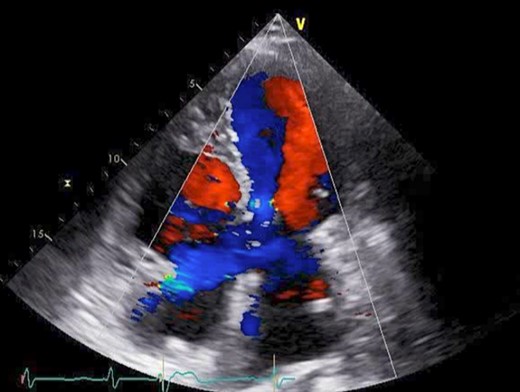

The patient had an uneventful postoperative course during her hospital stay. Echocardiography on postoperative Day 8 showed an EF of 64%, trivial MR, a mean PAP of 18 mmHg, and no shunt flow (Fig. 4). Therefore, the patient was discharged on the 19th day after surgery. The patient is doing very well 7 months after surgery.

Postoperative cardio echography showing an EF of 64%, trivial MR, mean PAP of 18 mmHg, and no shunt flow.